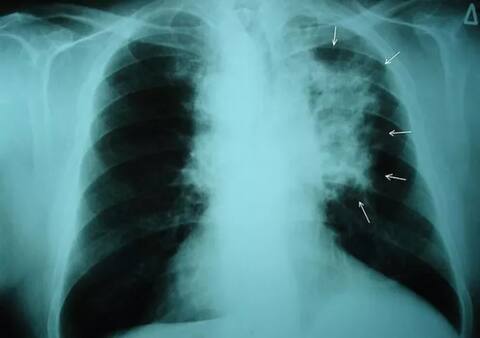

ਪ੍ਰਦੂਸ਼ਣ ਨਾਲ ਫੇਫੜਿਆਂ ਦੇ ਕੈਂਸਰ ਦਾ ਖ਼ਤਰਾ, ਇੰਝ ਕਰੋ ਬਚਾਅ

ਆਮਤੌਰ ’ਤੇ ਇਹ ਮੰਨਿਆ ਜਾਂਦਾ ਹੈ ਕਿ ਫੇਫੜਿਆਂ ਦੇ ਕੈਂਸਰ ਦੀ ਮੁੱਖ ਵਜ੍ਹਾ ਸਿਗਰਟਨੋਸ਼ੀ ਹੈ ਪਰ ਠੋਸ ਸਬੂਤ ਮਿਲੇ ਹਨ ਕਿ ਫੇਫੜਿਆਂ ਦੇ ਕੈਂਸਰ ਦੇ ਵਧਦੇ ਮਾਮਲਿਆਂ ਵਿੱਚ ਪ੍ਰਦੂਸ਼ਿਤ ਹਵਾ ਦੀ ਭੂਮਿਕਾ ਵੀ ਵਧ ਰਹੀ ਹੈ। ਇਸ ਖ਼ਤਰਨਾਕ ਬਿਮਾਰੀ ਤੋਂ ਬਚਾਅ ਲਈ ਤੁਸੀਂ ਜ਼ਿਆਦਾ ਪ੍ਰਦੂਸ਼ਣ ਵਾਲੀ ਥਾਂ 'ਤੇ ਮਾਸਕ ਪਹਿਨ ਕੇ ਜਾਓ।

ਵਧਦੇ ਪ੍ਰਦੂਸ਼ਣ ਕਾਰਨ ਲੋਕਾਂ ਵਿੱਚ ਫੇਫੜਿਆਂ ਦੇ ਕੈਂਸਰ ਦਾ ਸ਼ਿਕਾਰ ਹੋ ਰਹੇ ਹਨ। ਪਿਛਲੇ ਛੇ ਸਾਲਾਂ ਵਿੱਚ ਕੀਤੇ ਗਏ ਇੱਕ ਅਧਿਐਨ ਵਿੱਚ ਦਾਅਵਾ ਕੀਤਾ ਗਿਆ ਹੈ ਕਿ ਪ੍ਰਦੂਸ਼ਣ ਨਾਲ ਫੇਫੜਿਆਂ ਦਾ ਕੈਂਸਰ ਹੋ ਸਕਦਾ ਹੈ।